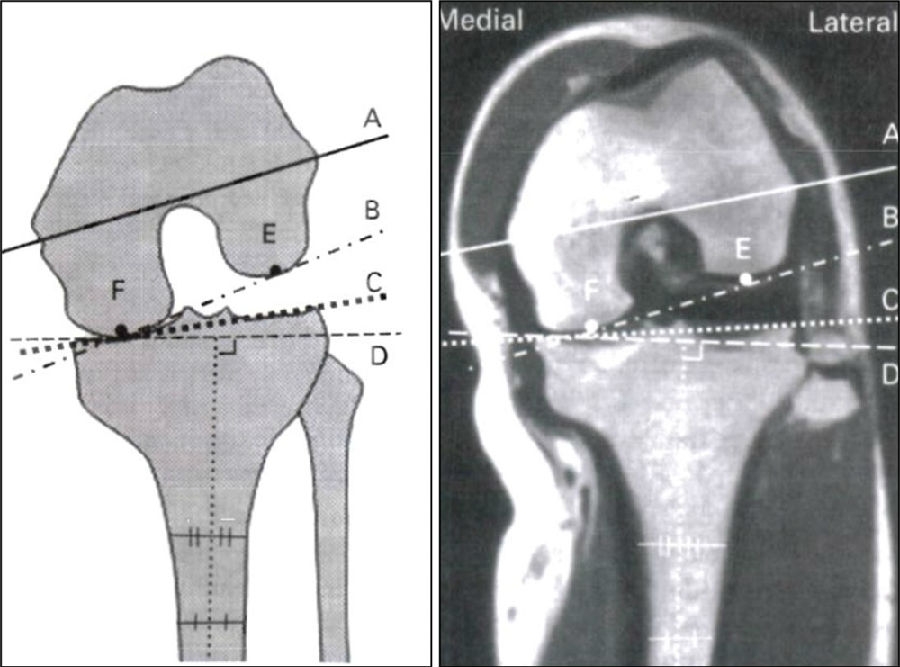

外侧胫骨平台相对于股骨外侧髁向外侧突出3-4mm, 股骨与胫骨平台解剖中线不一致。如果将股骨假体放置在股骨髁中央可能导致两个假体中心不一致,使股骨假体相对胫骨假体偏内。

股骨髁磨损;胫骨平台磨损

LCOA的磨损在胫骨平台后侧,股骨髁磨损从屈曲45°开始,随着病情发展逐步向前、向后,主要以后侧为主。LCOA早期时在伸直位通常没有畸形,当临床发现有外翻畸形时,此时病情已经发展较重。

关键技术3:股骨假体与胫骨假体中心一致

沿股骨外侧髁外侧缘安放股骨钻孔器,前缘与股骨髁标记线平齐,股骨与胫骨假体中心一致。

理想假体位置 A.股骨假体 胫骨假体中心线一致;B.股骨假体固定栓与后侧皮质呈35-40°

理想假体位置即前缘平稳过渡,后缘包容很好且不超出。